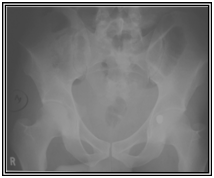

A 32 old male presented with a single gunshot wound to the right suprapubic area, with no exit. Radiographs revealed a bullet that appeared to be lodged in the left hip joint (Figures 1) A CT scan (Figures 2) and cystogram showed no associated injuries, with the bullet tract entering the quadrilateral surface of the left hip and the bullet buried in the posterior acetabular wall.

Figure 1 Radiographs at first presentation showing a bullet that appeared to be lodged in the left hip joint.